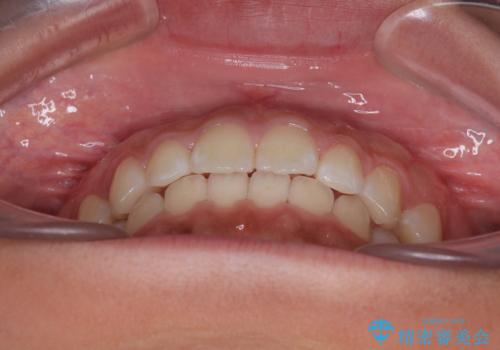

気になるすきっ歯を短期間で改善 インビザライン矯正

- 前歯の隙間を気にして来院された患者様です。

口元の突出感があり、小臼歯4本を抜歯して口元を引っ込める矯正治療も提案しましたが、本人は口元の突出感は気になっていないとのことで、インビザラインにて隙間やデコボコを改善することとしました。

軽度の歯列不正であったため、廉価版のインビザライン・モデレートパッケージにて治療を終えることができました。